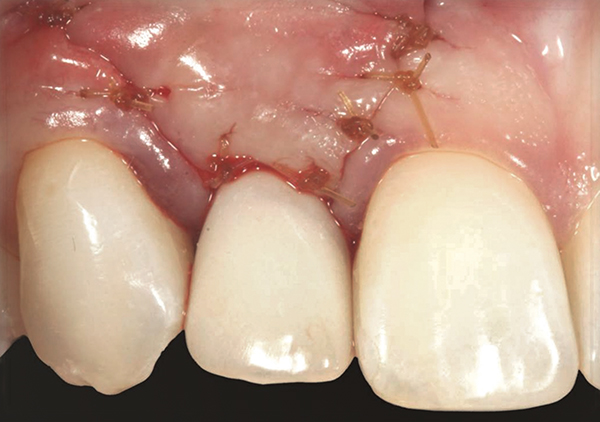

Fig 11. A horizontal releasing incision across the edentate ridge; it terminates 1 mm from the adjacent teeth.

Fig 17. Vertical and horizontal incisions were sutured to attain primary closure.